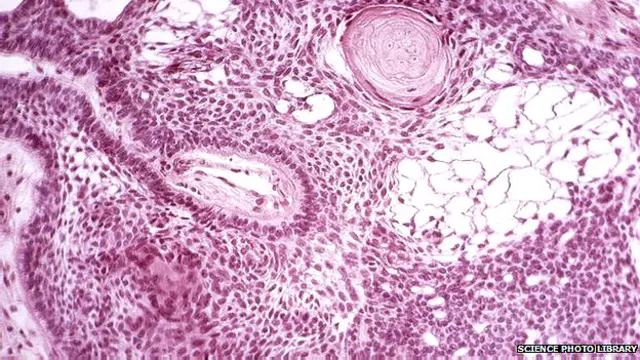

हार्वर्ड मेडिकल स्कूल के वैज्ञानिकों ने मस्तिष्क कैंसर से लड़ने के लिए स्टेम कोशिकाओं को एक किलिंग मशीन में तब्दील करने की अनूठी खोज की है.

चूहों पर किए गए एक प्रयोग में स्टेम कोशिकाओं को आनुवंशिक रूप से ऐसे तैयार किया गया है कि इनसे होने वाला विषाक्त स्राव सामान्य कोशिकाओं को नुकसान पहुंचाए बग़ैर मस्तिष्क के कैंसर को मार सके.

स्टेम सेल्स जरनल में प्रकाशित इस शोध पर मैसाच्युसेट्स जनरल हॉस्पिटल और हार्वर्ड स्टेम सेल इंस्टीट्यूट के वैज्ञानिकों ने काम किया था.

ये वैज्ञानिक कई साल से कैंसर के लिए स्टेम सेल आधारित इलाज़ पर शोध कर रहे थे जो केवल कैंसर कोशिकाओं को नुकसान पहुंचाती हैं.

उन्होंने स्टेम सेल तैयार करने के लिए अनुवांशिक इंजीनियरिंग का इस्तेमाल किया जो कैंसर को मारने वाले विषाक्त पदार्थ निकालते हैं. अहम बात यह है कि वे इस ज़हर के प्रभाव को रोकने में भी सक्षम हैं.